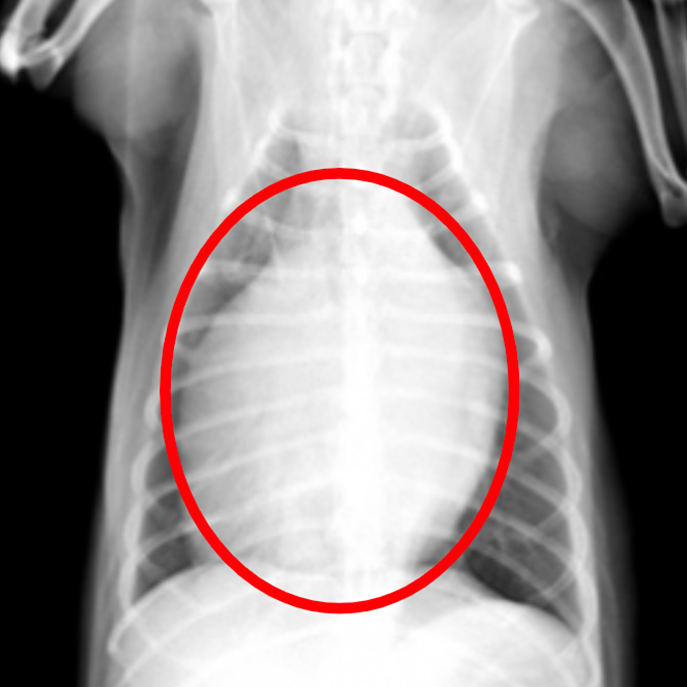

レントゲン検査

心臓の形や大きさ、肺、血管の太さのチェックをします。